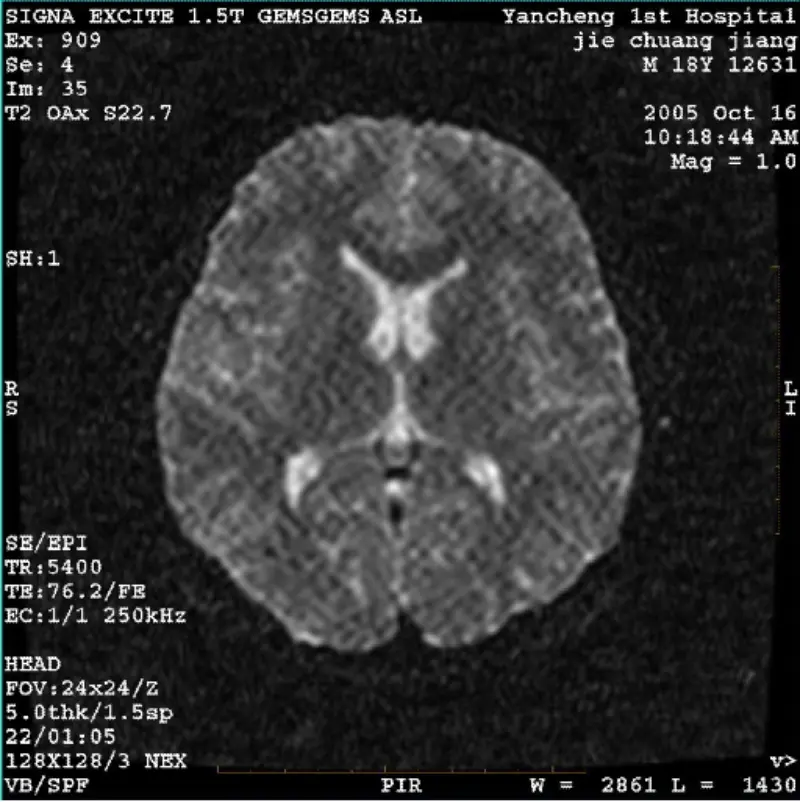

Loe rohkemSÜSTEEM: 1.5T Signa Twin Excite II (tarkvaraversioon 11.0M4) PROBLEEM/SÜMPTO DWI (suumirežiim ja kogu režiim) ja fiesta (suumirežiim ja kogu režiim) kujutis nähtav võrk või velvetist artefakt, olenemata kehaspiraali või pea kasutamisest mähis, muu rutiinne pilt tundub normaalne